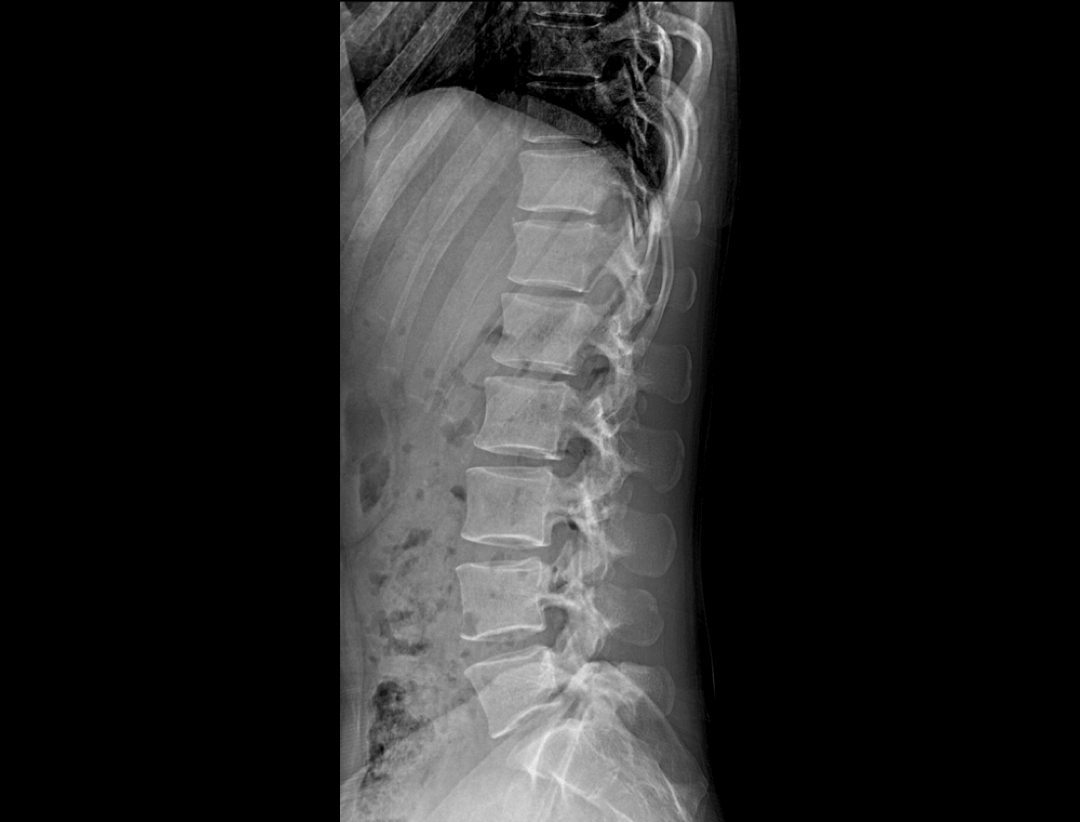

全自动无尺全景拼接*

支持自动立位无尺全景拼接,为骨科、整形外科提供高质量全景影像。

测量功能*

集成脊柱Cobb角及股骨颈干角测量功能,精准指导外科手术及术后评估。